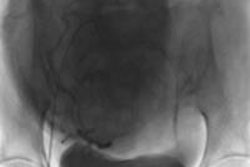

الأدوات التي تستخدم عادة في علاج الأورام الليفية الرحمية بالقثطرة:Robert catheter, microcatheter, and embolization particles.